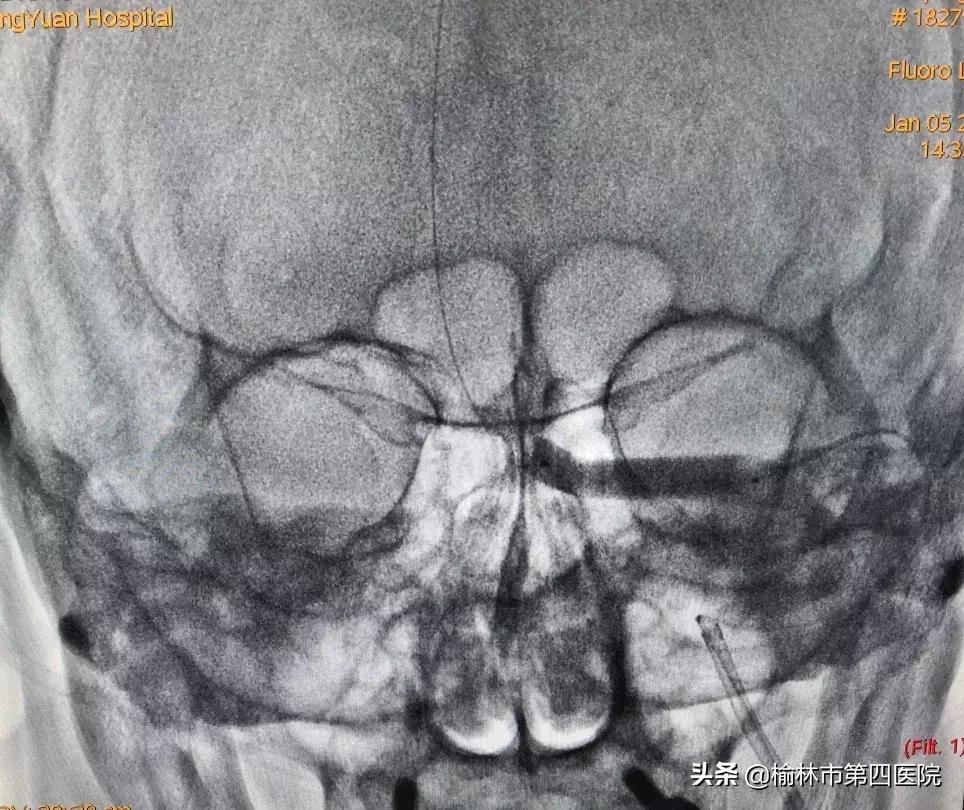

经过认真细致的准备,采取静脉麻醉下经股静脉入路的方案,术中股动脉造影导管和股静脉导引导管*管双**齐下,最终应用球囊序贯扩张左侧横窦狭窄段,因考虑到患者年龄较小,扩张后狭窄改善,故未予植入支架,为患者疏通了血流通道。